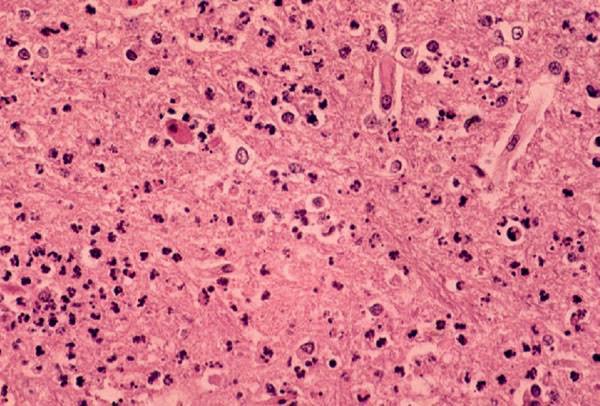

Информация о диссеминированном рассеянном энцефаломиелите